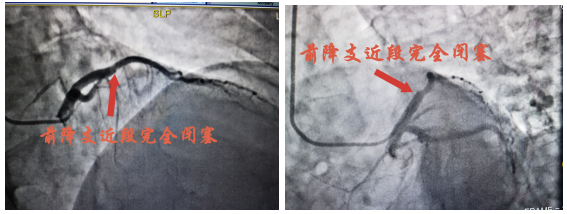

1月4日15:45左右,罗大爷再次出现胸痛,予以“硝酸甘油”舌下含服后无明显缓解,16:00复查心电图,考虑急性前壁ST段抬高型心肌梗塞超急性期,值班医生蔡波副主任医师查看患者后,建议立即行急诊冠状动脉造影及必要时支架植入术,尽早手术才能拯救更多的心肌,患者家属商议后同意并签署心导管诊疗同意书。

急性ST段抬高型心肌梗死(STEMI)是冠状动脉急性、持续性缺血缺氧所引起的心肌坏死,是最危重的心血管疾病。其特点是发病急、进展快、病情重,甚至在数分钟内即可发展为心脏呼吸骤停,甚至死亡。该疾病救治的宗旨是:时间就是心肌,时间就是生命。因此,尽快开通闭塞的冠状动脉,恢复其血流供应以减少心肌细胞死亡,保护心脏功能,是抢救的核心思想。